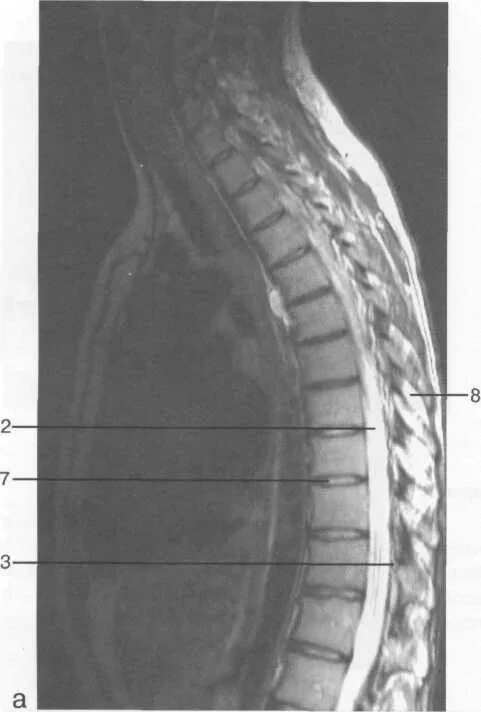

Деформация дурального мешка поясничного